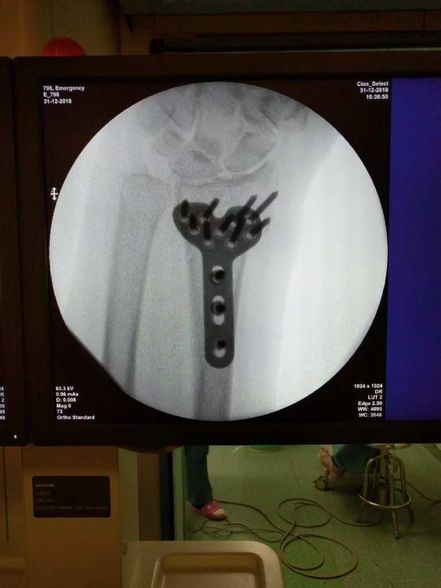

术后C臂机透视下的图片